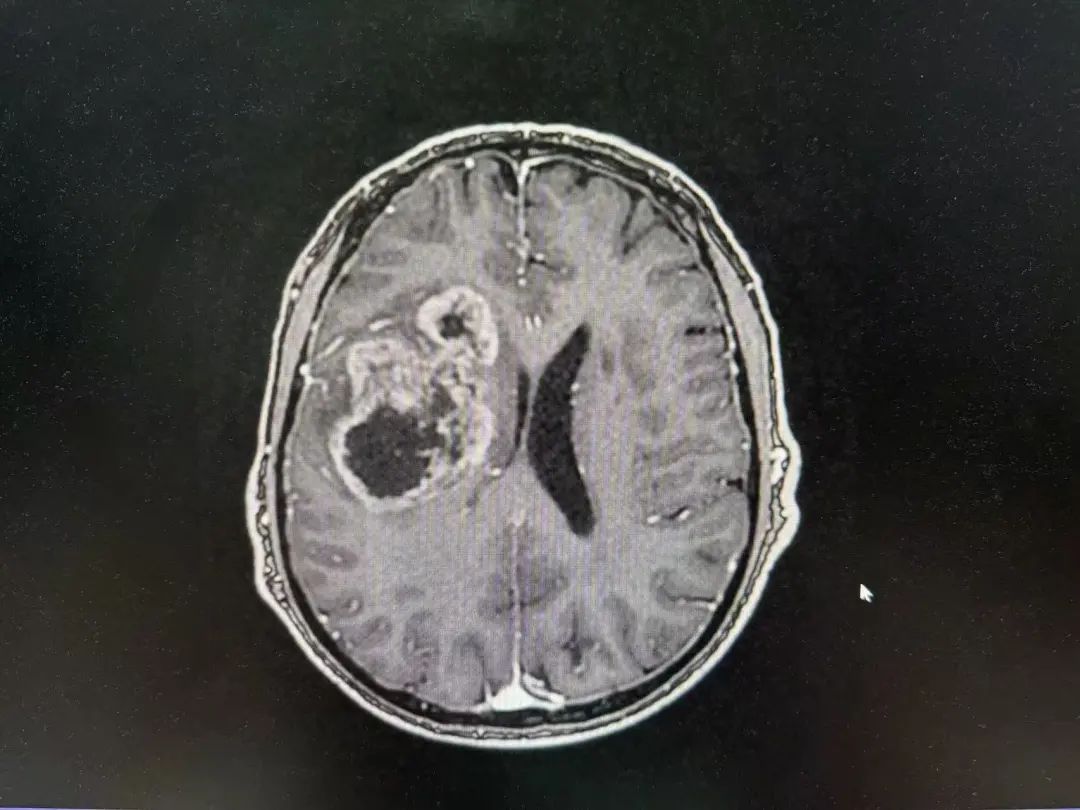

男性 | 67歲

主訴:左側(cè)口角流涎10天,左側(cè)肢體無力7天。

MR:右側(cè)大腦半球腫瘤性病變,考慮高級別膠質(zhì)瘤(大者大小約3.8cmx4.6cmx3.4cm)。